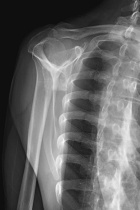

48 year old AAM with a two month history of a painful right shoulder and inability to reach overhead

Zoom image: Radiological image Radiological image.